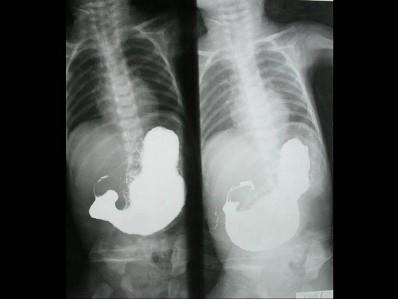

问题 男,6月。出生1月后经常出现喷射状呕吐,为奶块,渐加重。面色消瘦,右上腹部可触及核桃大小硬块。如图,最可能的诊断为?(?)

选项 A.胆总管囊肿 B.肠闭锁 C.先天性幽门肥厚狭窄 D.肠套叠 E.先天性巨结肠

答案 C